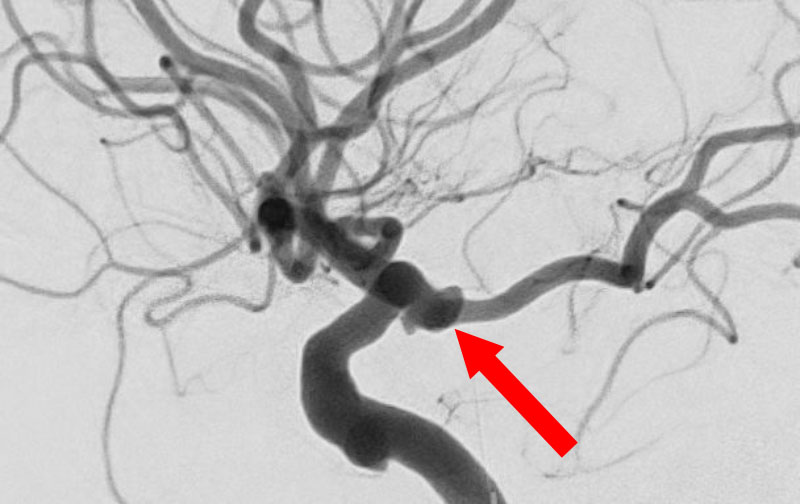

No.1631 手術前